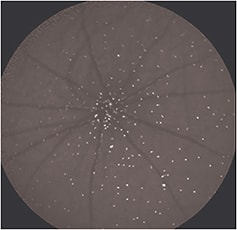

This method can quantify the number of apoptosing retinal cells (particularly retinal ganglion cells — RGCs) at a specific moment in time in vivo (Figure 2, page 50). With patient follow-up, it could potentially help to identify abnormal activity, monitor disease progression, and assess therapy.

Figure 2. An example of an image acquired using the DARC technique in a rat model, in which fluorescently labeled Annexin marks retinal ganglion cells undergoing apoptosis in vivo, each cell identified by a white spot.

The technique uses fluorescently tagged Annexin-V, injected intravenously, to identify cells with externalized phosphatidylserine.3 We can then count these cells to assess the current level of apoptosis. Phase 1 clinical trials are due to begin shortly to establish safety and proof of concept in patients.3-5